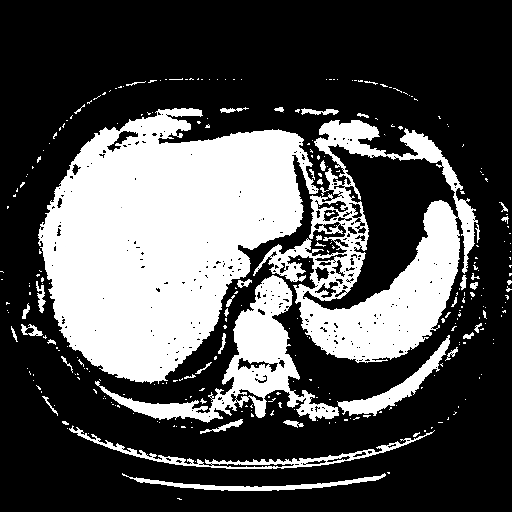

Generated VENOUS CT scan (A→B translation)

Full window (WL 1023.5, WW 4095 β†’ Low βˆ’1024, High +3071)

Actual HU range: [-1024.0, 3071.0]